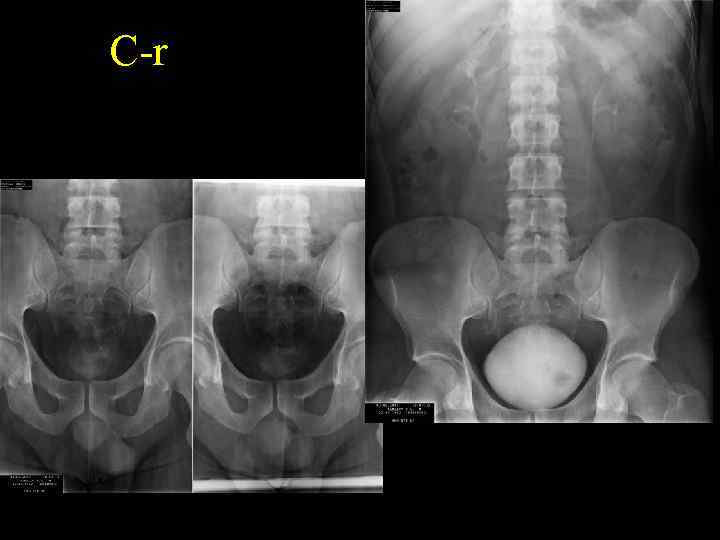

С-r